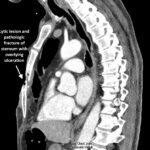

This case highlights a rare and complex occurrence of an open chest wound with a pathologic sternal fracture. This resulted from a combination of remote chest trauma, chronic chest wall infection, malignancy, and ultimately, sternal osteomyelitis. A 69-year-old male presented with a large, open anterior chest wound, chronic ulceration, and weight loss. Thirty years earlier, the patient had sustained trauma from a firecracker, which led to a chronic wound for which he did not seek medical attention. Physical exam revealed a large open chest wound with an open sternal fracture and exposed pericardium. The patient underwent surgical resection, followed by chest wall reconstruction using a rectus myocutaneous flap. Tissue pathology confirmed squamous cell carcinoma and osteomyelitis of the sternum.

The case demonstrates the complexity of managing a large chronic chest wound and pathologic sternal fracture secondary to malignancy and osteomyelitis. The key lesson is the importance of early medical evaluation and a multidisciplinary approach to improve outcomes in similar scenarios. The rarity of this case emphasizes the need for heightened awareness among clinicians who may encounter earlier presentations of this disease process in order to prevent complications, such as osteomyelitis, pathological fractures and structural instability of the chest wall.